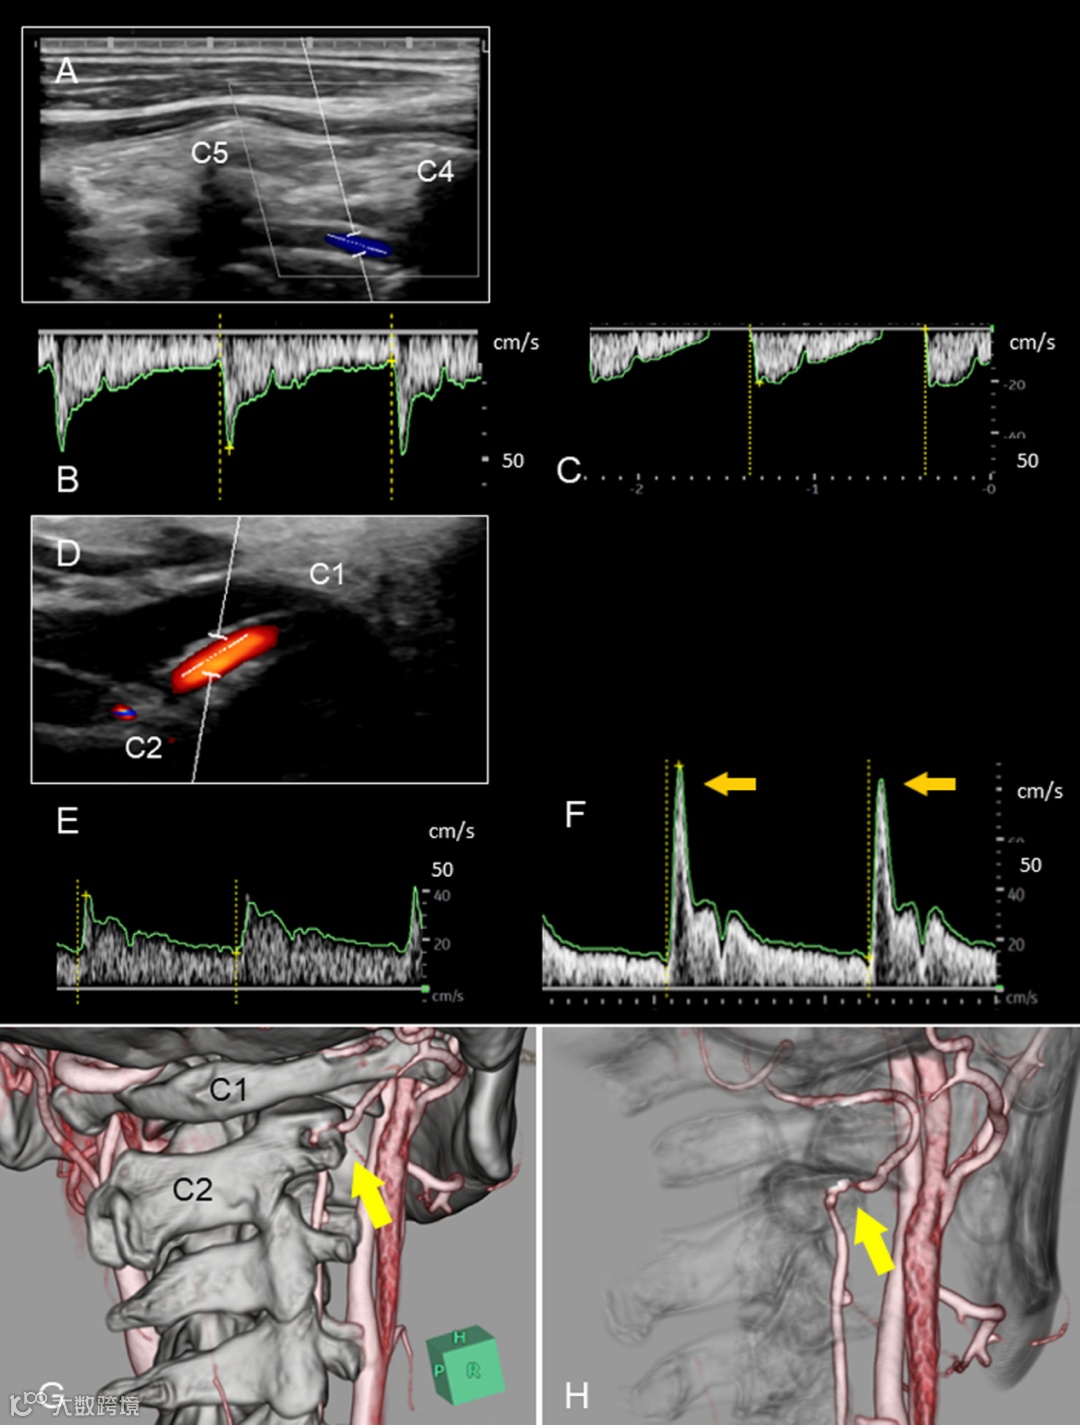

颈动脉超声显示,中立位时右侧椎动脉 C4/5 水平血流正常;头部向左旋转后,右侧椎动脉舒张末期流速消失(图 A-C);C1/2 水平(紧邻 2 水平远端),颈部逐渐向左旋转时,右侧椎动脉收缩期血流先加速后消失,提示存在阻塞点(图 D-F)。

患者采取超声引导下 CTA 检查,显示颈部向左旋转时右侧椎动脉 C1/C2 水平存在狭窄(图 G、H),与超声检查结果一致。